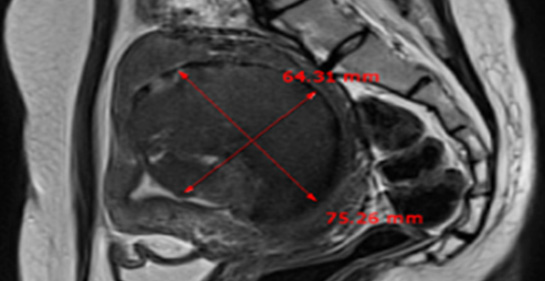

MRI촬영으로 자궁근종의 상태(위치, 개수, 크기, 모양 등), 자궁근종의 혈액공급 및 혈류,

자궁근종과 인접한 주요장기 및 구조, 초음파 발사경로의 확보 등을 분석함.

또한, 정밀초음파는 제거할 자궁근종의 개수, 자궁근종의 치료 슬라이스 수와

각 슬라이스의 체적, 근종제거마진, 근종과 인접한 장기와의 상관관계 등을 분석합니다.